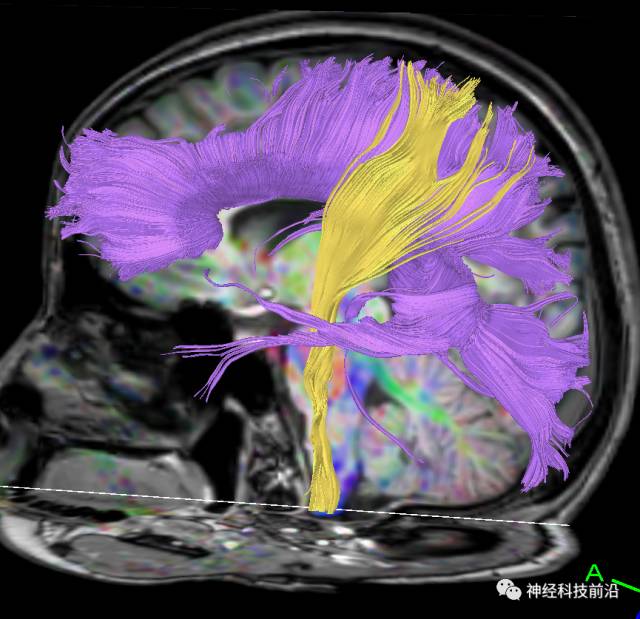

皮质脊髓束与皮质脑桥束的关系毗邻